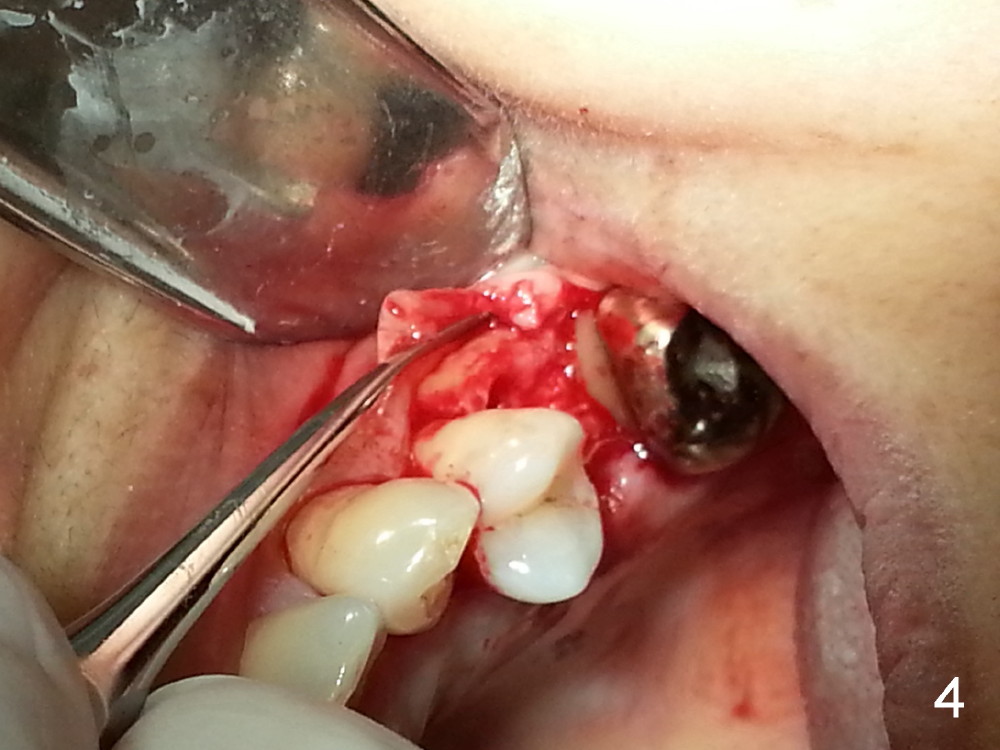

Grafting Following Immediate Implant (Photos Provided by Xue Steven, DDS)

The tooth #13 appears to be affected by periodontits and occlusal trauma (Fig.1*). After using a periotome (Fig.2), the tooth is extracted (Fig.3). The buccal flap is raised (Fig.4). Gingival graft is to be harvested from the site of #15 (Fig.5). The tissue is elevated buccally (Fig.6) and separated (Fig.7). The donor site is covered by a collagen membrane (Fig.8*). A diamond bur is used to induce bleeding from the socket (Fig.9*). Osteotomy is initiated (Fig.10) and enlarged (Fig.11,12). A tapered implant is being placed (Fig.13-15) following internal sinus lift (Fig.16,17). The implant is placed subcrestally, followed by bone graft (Fig.18), soft tissue graft (Fig.19), and suturing (Fig.20 <, Fig.21).